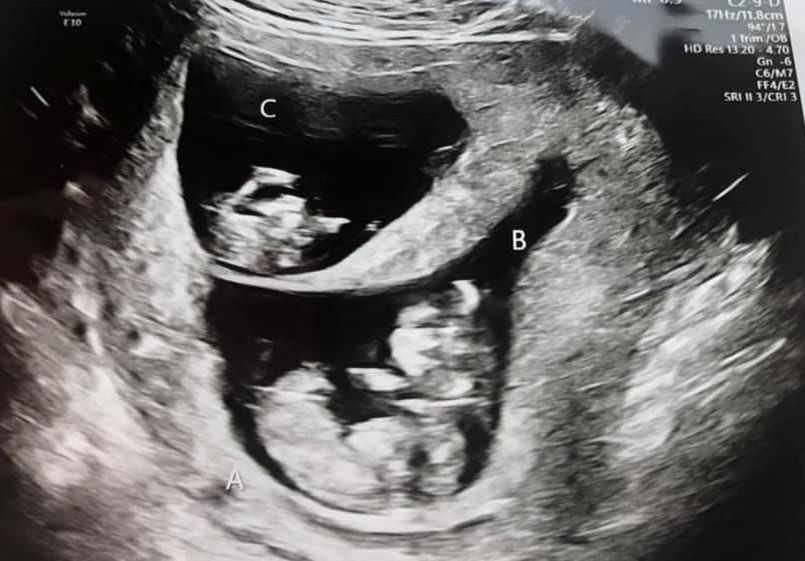

- Zdecydowaliśmy się umieścić dwa embriony, ponieważ uznaliśmy, że w ten sposób zwiększymy nasze szanse na dziecko. Lekarze powiedzieli nam, że istnieje 10 proc. szans, że będą to bliźnięta i jeden procent, że będą to trojaczki. Nigdy nie spodziewaliśmy się takiego scenariusza – mówi Kaylie. - Kiedy dowiedzieliśmy się, że mamy troje dzieci, byliśmy w szoku, ale to było niesamowite. Bylibyśmy szczęśliwi z jednym dzieckiem, a się okazało, że będzie ich więcej – dodaje.

Okazało się, że Kaylie jest w ciąży z trojaczkami

Niestety taka ciąża wiąże się z ogromnym ryzykiem. W 16. tygodniu odkryto, że szyjka macicy nie jest w stanie wytrzymać takiego obciążenia i trzeba ją zszyć. Już wtedy Kaylie miała dwucentymetrowe rozwarcie.